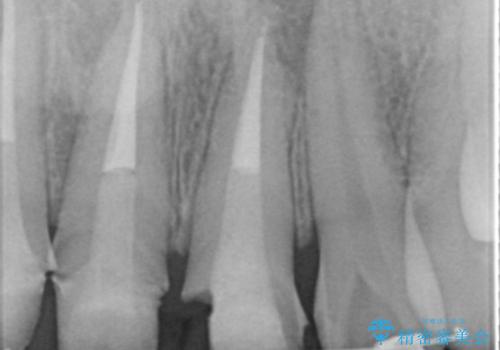

視診・X線検査・歯周組織検査より下記のような問題が列挙され、長期的な予後を見込むために一つづつ問題の解決を計ります。

・不十分な根管治療 →マイクロスコープを用いる精密根管医療